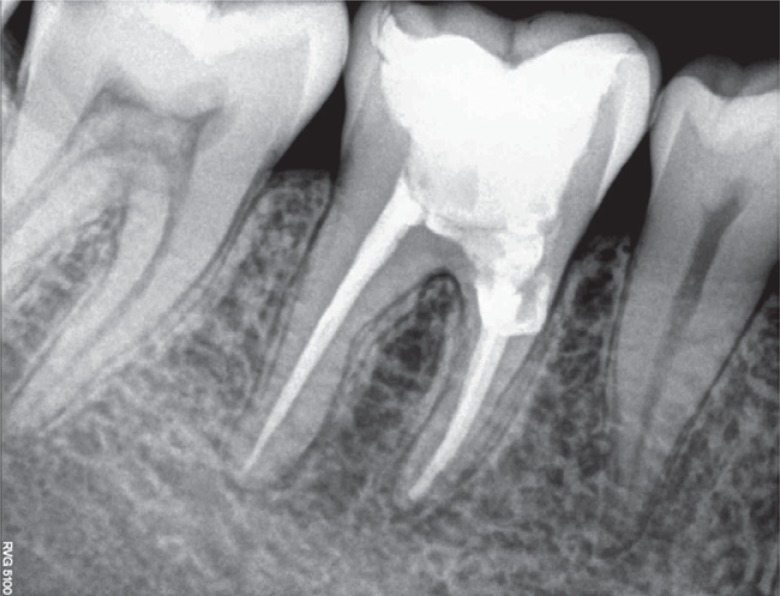

9). The patient returned for follow-up after 6, 12, and 20 months, and the radiographs revealed appreciable healing in the periapical area (

Figures 10,

Figure 10Six month follow-up radiograph.

Figure 11One year follow-up radiograph showing appreciable healing in the periapical area.